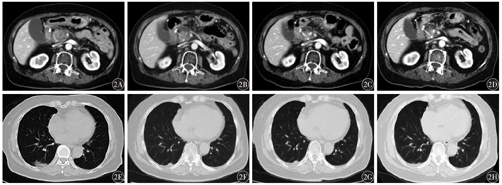

(1)获得SD的患者为女性,64岁,2019年9月行胰腺癌手术,术后行放疗,后复查未见复发。2020年7月确诊为胰腺癌术后肠系膜上动脉周围转移,8月开始予信迪利单抗治疗。经信迪利单抗联合白蛋白结合型紫杉醇规律用药6个周期,疗效评价为SD,后予信迪利单抗单药维持治疗2个周期。至末次治疗(2021年4月2日),仍处于SD状态;不良反应主要为1级乏力,未影响治疗。(2)获得PR的患者为女性,74岁,2019年4月确诊为胰腺癌伴肺、淋巴结转移,无手术适应证,予局部姑息放疗后经多线化疗后进展。2020年4月开始予信迪利单抗治疗,治疗不规律,经信迪利单抗治疗2个周期后,腹泻症状明显好转,肿瘤指标CA199从645.0 U/ml降至80.2 U/ml,病灶缩小47.6%,疗效评价为PR。应用信迪利单抗治疗至末次治疗(2021年4月30日)期间,出现一系列不良反应,包括皮疹、甲状腺功能亢进、甲状腺功能减退、尿路感染、高尿酸、高血糖、肾功能不全,皆为1~2级,经对症治疗后好转。患者处于持续缓解中。该患者信迪利单抗治疗期间肿瘤相关指标及不良反应变化情况见表1,信迪利单抗治疗前后胸部及腹部病灶影像学变化见图2。